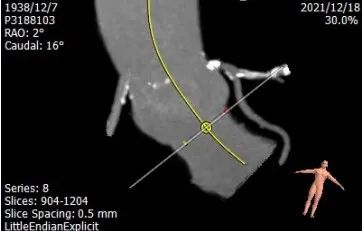

主动脉成角:58°

手术策略:采取全麻下,经右侧股动脉为主入路,通过ICD实现快速起搏。选用VitaFlow Liberty™可回收瓣膜TAV 30型号植入。目标植入深度在瓣环下4 mm。